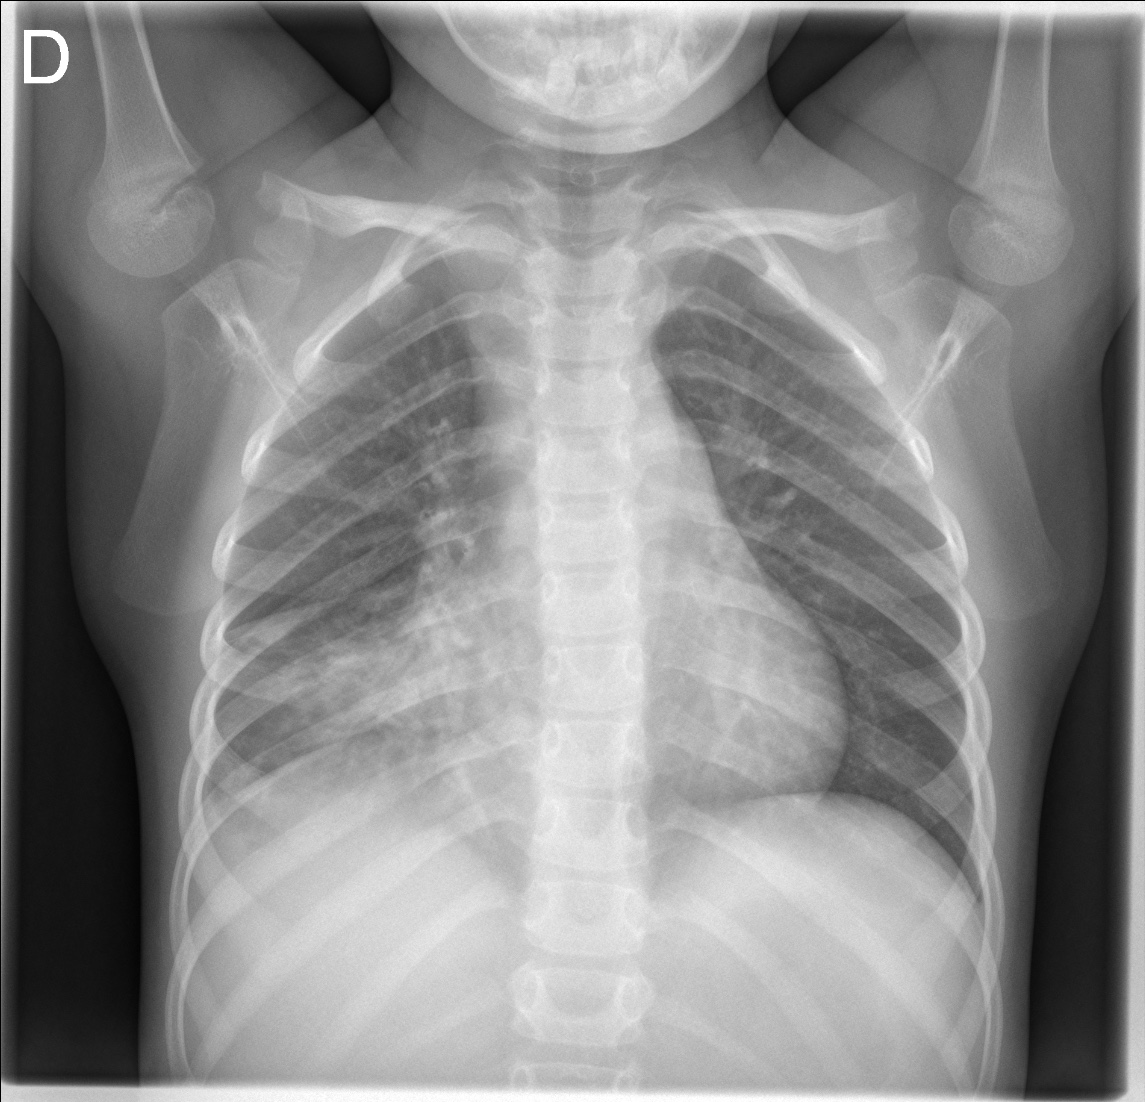

CASO: Operada de esofaguectomia y reconstrucción con coloplastia hace 3 meses. Sintomas de neumonía.

Hallazgos:

- De inicio llama la atención una densidad practicamente total del todo el hemitórax izquierdo, lo cual podría hacernos pensar que estamos ante una posible neumonía.

- Sin embargo el tórax está no está bien centrado, observar como la clavícula izquierda se encuentra casi en la mitad del pulmón, por tanto lo que vemos blanco es el mediastino ya que el tórax está rotado.

CENTRAJE:

El correcto centraje se determina comprobando que las extremidades internas de ambas clavículas equidistan de las apófisis espinosas vertebrales.

Mismo paciente, al cual esta vez se le ha tomado una radiografía en PA y en sedestación. Observar como las clavículas están equidistantes a las apófisis espinosas y como ha desaparecido el velamiento del pulmón izquierdo.

Por otra parte, paciente presenta una cardiomegalia y un discreto ensanchamiento del mediastino es probable relación con cambios postquirúrgicos.